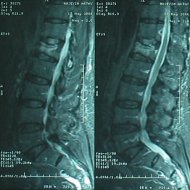

Kemik Erimesine (Osteoporoz) Bağlı Omurga Kırığı: İleri yaşta osteoporoz, yaşlılık ve/veya menopoza bağlı kemik kitlesinin azalması nedeniyle oluşur. Kemikleri zayıflatan bu sorun nedeniyle basit travmalarda bile kemikler kırılabilir hale gelir. En çok kırılan kemikler omurga ve kalça kemikleridir. Osteoporozun çok ileri olduğu bazı durumlarda hasta aksırınca bile omurgası kırılabilir. Bu durumda hastaya kemik çimentosuyla dolgu tekniği (vertebroplasti) uygulanabilir. Ancak tekrarlayabileceği göz önünde bulundurularak kemik erimesine yönelik ilaç tedavisi unutulmamalıdır. Hastalarda en sık ortaya çıkan şikayet sırt ya da bel ağrısıdır. Bazen çökme kırıkları sonucu olan ağrı hastayı çok rahatsız etmez ama oluşan deformite sonucu hasta doktora başvurur. Yaşlılarda Kifoz: Yaşlanan omurgada hem osteoporotik kırıklar hem de disklerde oluşan dejenerasyonla beraber kifoz oluşabilir. Bu durum bir yandan hastada solunum sorunları oluştururken diğer yandan günlük aktiviteleri kısıtlar. Yaşlılarda Skolyoz: İleri yaşta skolyoz ya dejeneratif omurga sorunları sonucunda ya da geçmişte var olan skolyozun artmasıyla oluşabilir. Birinci durum sinirlere bası nedeniyle sıklıkla bacaklara yayılan ağrı ile beraberdir.

Kemik erimesine (osteoporoza) bağlı omurga kırığı olan hastada vertebroplasti (çimento ile dolgu) tedavisi